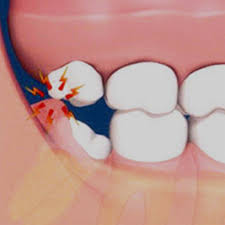

사랑니는 치아 중 가장 나중에 나고 자라므로 턱뼈에 공간이 부족하면 똑바로 나오지 못하고 주변의 잇몸을 괴롭히면서 통증을 유발한다고 한다.

▶사랑니가 똑바로 나지 않고 비스듬히 난 경우 ▶사랑니 주변 잇몸이 자꾸 붓고 아픈 경우 ▶사랑니와 그 앞 어금니 사이에 음식물이 자주 끼는 경우 ▶사랑니에 충치가 생겼으나 치료가 어려운 경우 ▶사랑니 앞의 어금니를 치료해야 하는데 사랑니로 인해 정상적인 치료가 어려운 경우 ▶교정치료를 해야 하는데 사랑니가 방해가 되는 경우 ▶X선 검사 소견 상 사랑니 주변에 혹으로 의심할 만한 부분이 나타난 경우 사랑니를 반드시 빼야 한다고 한다.

한 대학병원 치과 교수는 “젊을 때 빼지 않아도 되는 사랑니라고 판정받았어도 나이가 들면서 사랑니를 빼야 하는 사례가 생긴다”며 “나이 들수록 잇몸뼈의 양이 줄어 사랑니가 뼈 밖으로 살짝 나오면서 주변 잇몸과 인접한 치아를 계속 자극해 통증과 충치를 유발한다”고 말했다고 한다.